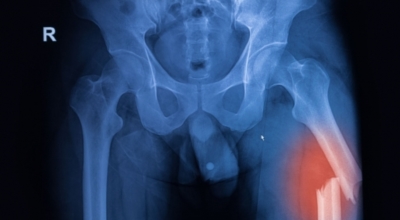

고관절 통증 치료에는 크게 약물 치료와 물리 치료가 있어요. 고관절염의 진행을 늦추거나 증상을 개선하기 위한 목적으로 항염증제 또는 진통제를 투여합니다. 고관절 질환의 일부 증상은 체외 충격파, 물리치료, 약물치료 과 같은 비수술 요법으로 증상이 호전될 수 있답니다.

그러나 비수술 치료법으로 개선시키는 것이 어려운 경우 수술적 방법이 고려됩니다. 고관절 통증을 조기에 치료하면 약물치료 외에 물리치료로 약 50% 정도 큰 효과를 볼 수 있어요. 게다가, 보통 고관절 증상 관리에 도움되는 요가, 수영, 스트레칭은 고관절 예방과 치료에 도움 됩니다.